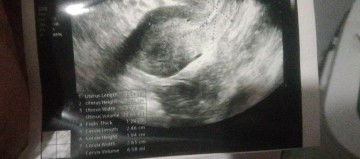

Sino dito same case ganto 😭 july 12 nag positive sa serum pregnancy test then July 15 dinugo 4days yun tapos binigyan ako pampakapit kinabukasan wala na pag dugo mga pt ko faint line then puro ako endo thick una 1.24cm pangalawa 0.84cm tapos ngayon August 18 dinugo ako 4days days din yun hindi kona expect na buntis ako kasi dinugo ako twice e 🥺

Ano ibigsabihin ng endo thick sa ultrasound

Endo thick?